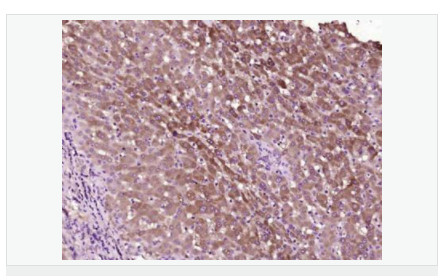

交叉反應(yīng):Human,Mouse,Rat(predicted:Phosphotyrosine) 推薦應(yīng)用:IHC-P,IHC-F,ICC,IF

| 產(chǎn)品應(yīng)用 | IHC-P=1:100-500 IHC-F=1:100-500 ICC=1:100-500 IF=1:100-500 (石蠟切片需做抗原修復(fù)) not yet tested in other applications. optimal dilutions/concentrations should be determined by the end user. |

| 產(chǎn)品介紹 | The phosphorylation of specific tyrosine residues has been shown to be a primary mechanism of signal transduction during normal mitogenesis, cell cycle progression and oncogenic transformation, its role in other areas such as differentiation and gap junction communication, is a matter of active and ongoing research. Antibodies that specifically recognize phosphorylated tyrosine residues have proved to be invaluable to the study of tyrosine phosphorylated proteins and the biochemical pathways in which they function. SWISS: N/A CAS: 21820-51-9 Important Note: This product as supplied is intended for research use only, not for use in human, therapeutic or diagnostic applications. |